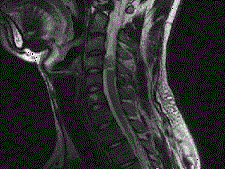

问题 男,24岁,颈部疼痛,并右上肢麻木,以手部明显,请根据所提供图像,选择最可能的诊断 ( )

选项 A、(颈4~5)血管母细胞瘤 B、(颈4~5)胶质瘤 C、(颈4~5)脊膜瘤 D、(颈4~5)海绵状血管瘤 E、(颈4~5)神经鞘瘤

答案 E